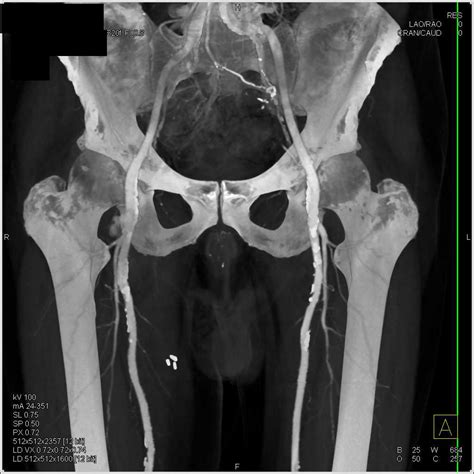

Physicians use various imaging techniques to confirm the presence of a femoral artery aneurysm and assess its size, location, and potential for complications. Accurate diagnosis is vital for planning the appropriate treatment path.

CT Angiography (CTA) Provides highly detailed cross-sectional images to map the vascular anatomy and plan for potential surgery.